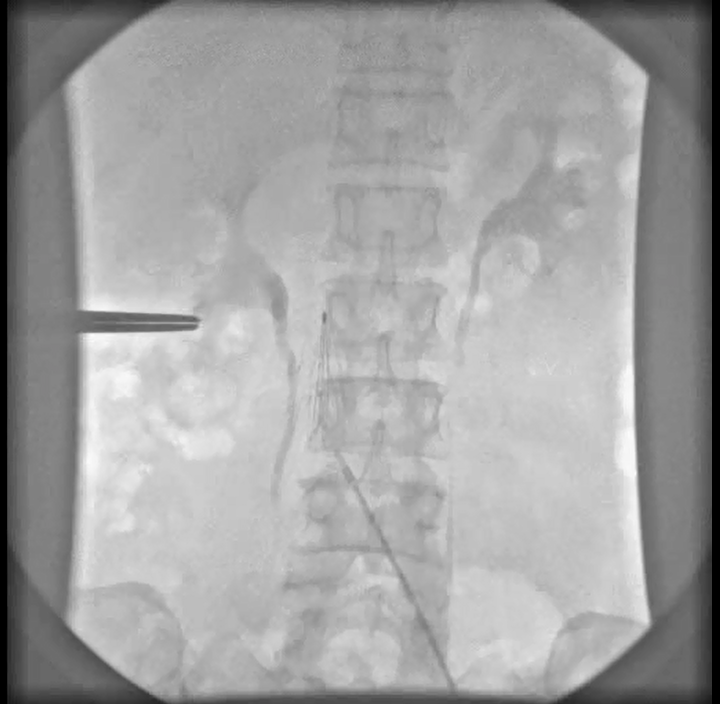

Đặt lưới lọc tĩnh mạch chủ dưới là biện pháp tạm thời hay vĩnh viễn cho người bệnh có huyết khối tĩnh mạch chi dưới. Đây là phương pháp an toàn và có hiệu quả cao trong dự phòng tắc nghẽn động mạch phổi do huyết khối di chuyển mà người bệnh lại không dùng được thuốc chống đông.

Mục đích của phương pháp đặt lưới lọc là để ngăn chặn các huyết khối di chuyển lên buồng tim và tuần hoàn phổi.

Một trường hợp đăt lưới lọc Option Elite vào tĩnh mạch chủ dưới đoạn dưới tĩnh mạch thận phải